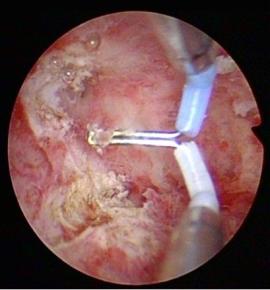

宫腔镜下显示的宫腔粘连

图片尺寸477x444